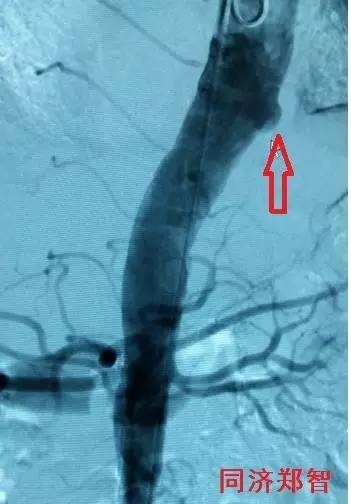

DSA造影显示降主动脉穿透性溃疡(图8)。

图8